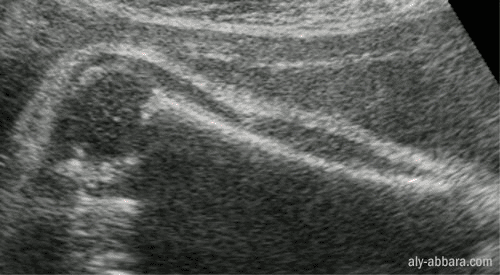

L'humérus ftal

(l'os du bras) : les parties ossifiées de l'os

à 35 semaines

d'aménorrhée

Coupe

longitudinale

On peut distinguer

sur cette image échographique les parties ossifiées de l'humérus

à ce terme de grossesse, à savoir, la diaphyse et le pôle

inférieur de la tête de l'humérus.